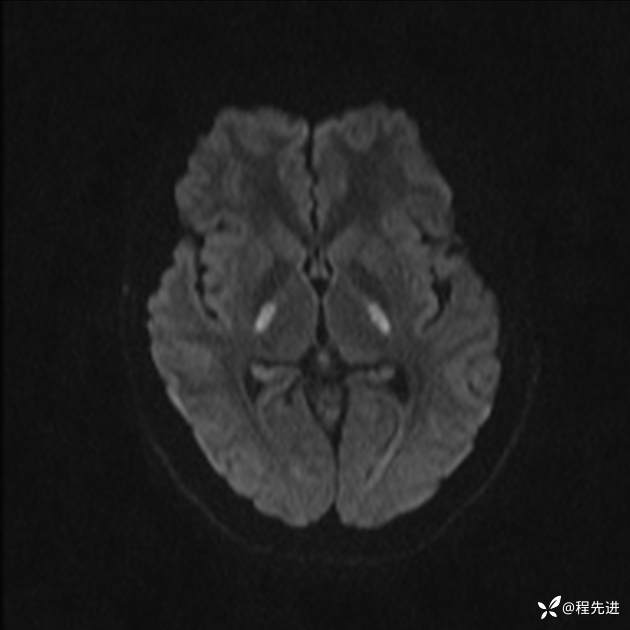

【患者信息】:女,25岁

【现病史及既往史】:言语含糊、意识状态改变1天。有下段剖宫产术10天病史。